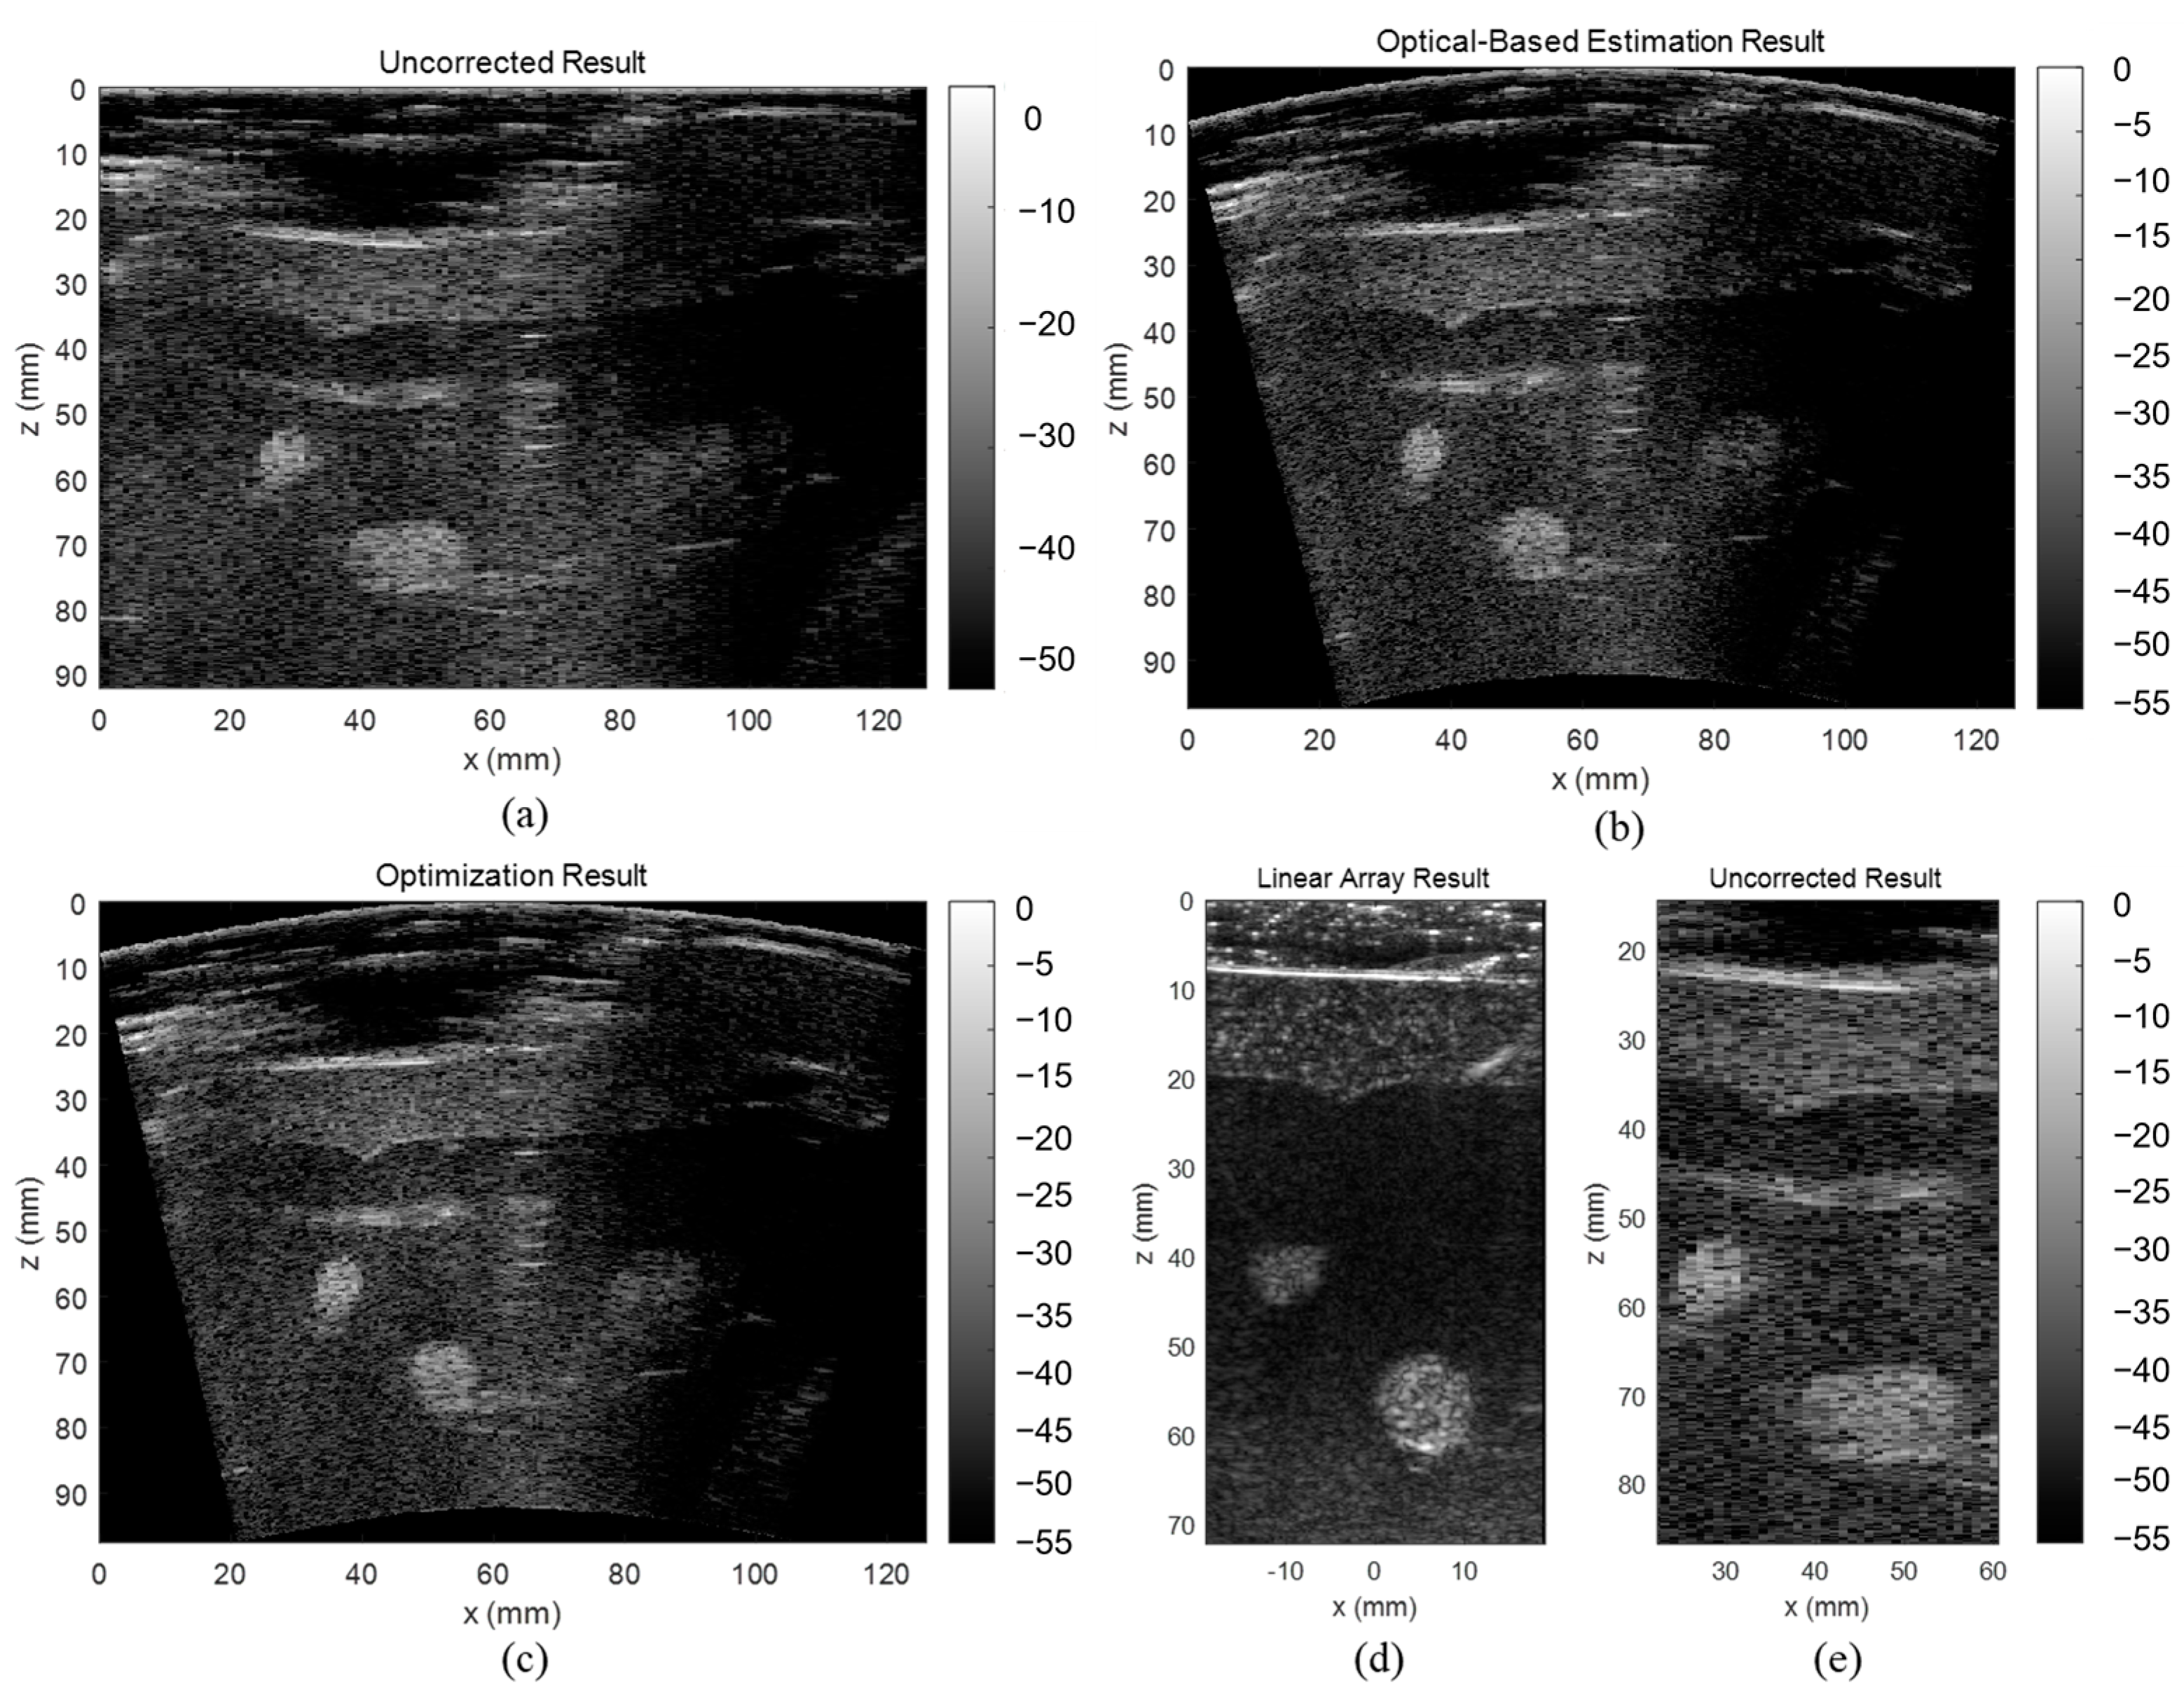

3.3. ABDFAN Phantom and Liver Scan Results

The uncorrected, optical-based estimation, and optimization results of the ABDFAN phantom and liver scan are shown in Figure 10 and Figure 11. The ground truth images from the linear array transducer are shown in Figure 10d and Figure 11d, and the same regions are cropped from the flexible array transducer results, and examples of the uncorrected results are depicted in Figure 10e and Figure 11e. The uncorrected results have significant distortions compared with the ground truth and corrected results. To quantitatively analyze the distortion, the cysts, blood vessels, and mussels are segmented as shown in Figure 12, and the Dice score, Jaccard index, and Hausdorff distance between the results and ground truth are evaluated and listed in Table 5, Table 6, and Table 7. The results show that both estimation and optimization algorithms can correct the distortions of the reconstructed image, and there is no significant difference between the two algorithms. The CNR and GCNR of the center cyst in the ABDFAN phantom and the large blood vessel in the liver scan are listed in Table 5, Table 6, and Table 7. In conclusion, the images reconstructed by both algorithms have an overall higher accuracy and contrast than the uncorrected images, and the optimization algorithm has a slightly better performance on estimating the array shape.

Figure 11.

Reconstructed images of the liver scan (a) without array shape correction, (b) with optical-based estimated shape and (c) optimized shape, (d) ground truth image from the linear array transducer, and (e) cropped image with the same region as the ground truth.